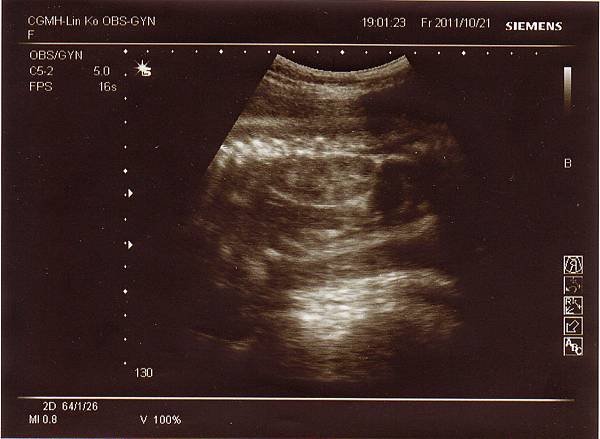

醫生說我的肚子真的不大,但寶寶的成長還是正常範圍,

比他想像中的好很多(原以為肚子太小寶寶也會很小),